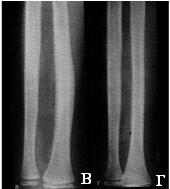

Діафізарний остеомієліт Гарре частіше зустрічається у молодих чоловіків. Процес в більшості випадків локалізується в області діафіза великогомілкової або стегнової кістки. Уражена ділянка кістки веретеноподібно потовщується за рахунок періостальних нашарувань, що охоплюють кістку у вигляді муфти. Іноді потовщення має асиметричний вигляд. Костномозговой канал звужений або повністю закритий за рахунок ендостальною остеосклероза. Вогнищ деструкції та секвестрів зазвичай не буває (рис. 5).

Мал. 5. Первічнохроніческій остеомієліт Гарре. Потовщення і ущільнення ділянки діафіза великогомілкової кістки за рахунок периостального і ендостальною костеобразования.